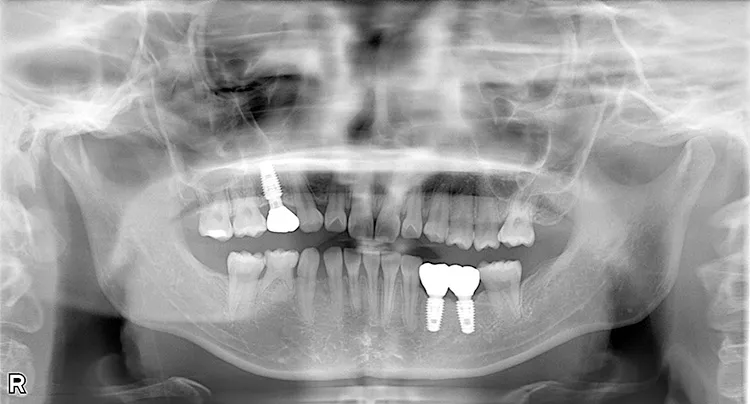

レントゲン画像

症例1/

臼歯2本

- 治療期間

- 10ヶ月

- 費用

- 90万円(税込)